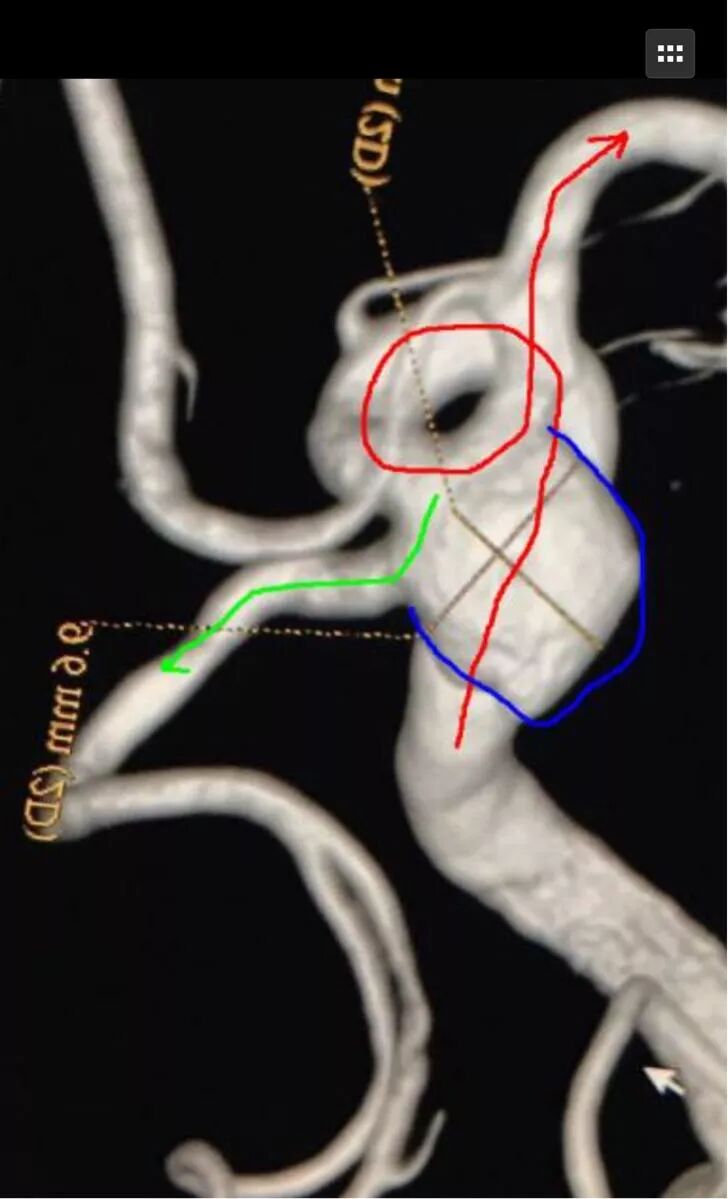

我们来看看动脉瘤的结构:红色为颈内动脉走向,绿色为后交通动脉走向,蓝色为动脉瘤

栓塞的要点,既要致密填塞,又要保证颈内动脉和后交通动脉的通畅。决定通过对侧前交通动脉-颈内动脉远端-后交通动脉途径来置入输送支架的微导管,从后交通动脉释放支架直到颈内动脉末端,以达到一个支架对颈内动脉和后交通动脉的保护